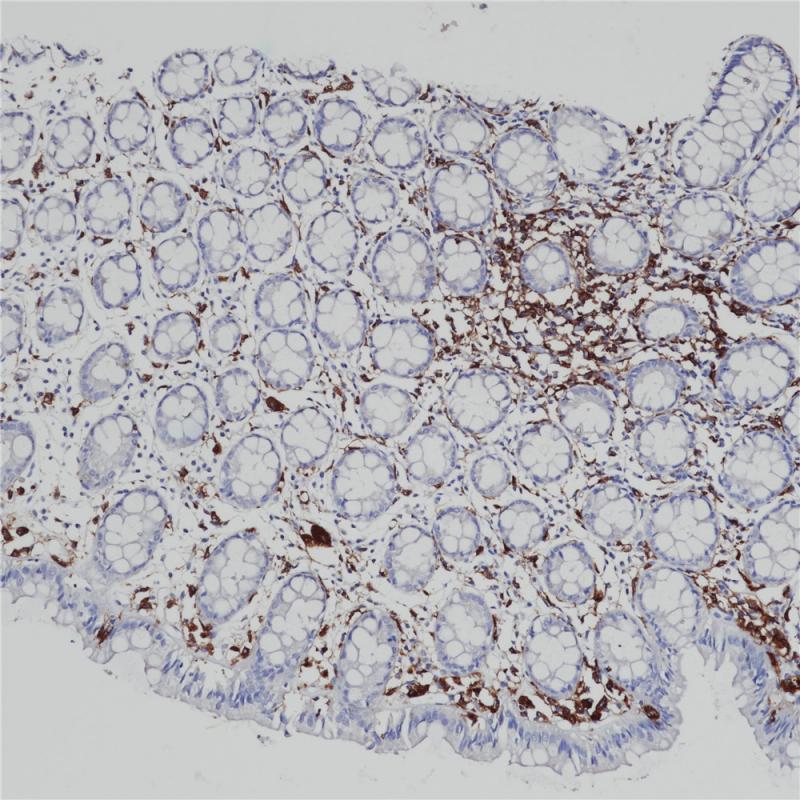

MHC II(DRα chain) 重组兔单克隆抗体

主要组织相容性复合体 II 类(MHC II 类)分子是在巨噬细胞、树突细胞和 B 细胞等抗原呈递细胞表面表达的异二聚体的跨膜糖蛋白。在人体中,MHC II 类蛋白复合体被人白细胞抗原基因复合体 (HLA) 编码。MHC II可在 B 淋巴细胞、活化的 T 淋巴细胞、活化的自然杀伤 (NK) 细胞等表达。

阳性对照

食管